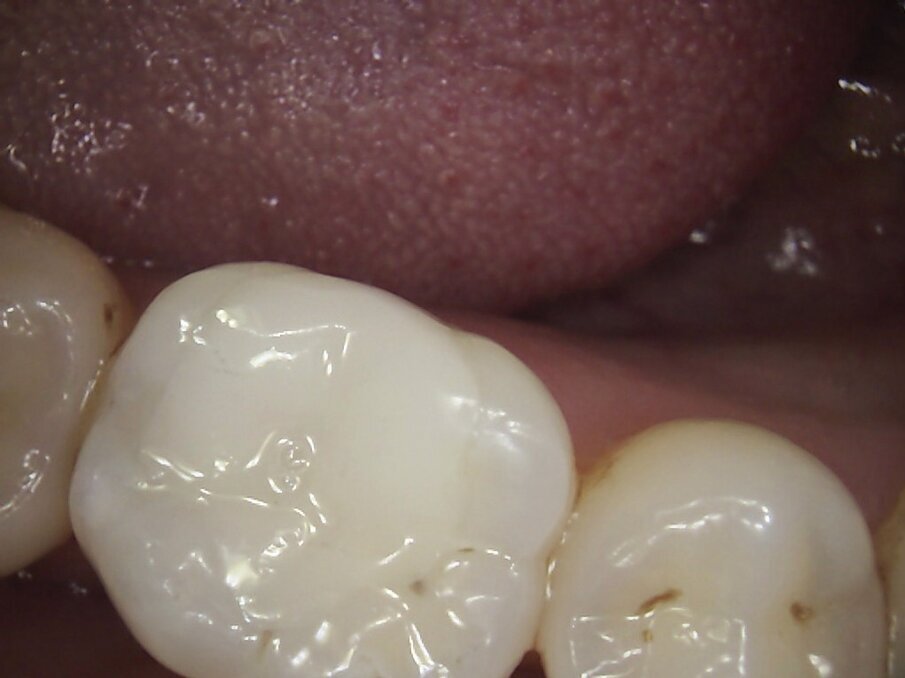

On examination, teeth 16 and 46 had amalgam restorations, with defective margins and signs of corrosion of the metal into the surrounding dentinal tubules. Tooth 46 had a vertical fracture running from occlusal surface to 1mm coronal if the gingiva on the palatal aspect. Neither tooth was tender to percussion and both scored positively with electric pulp testing. However, 46 did have pain on release when biting on the palatal cusps of the crack finder. The patient confirmed this was the sensation she had been experiencing over the last few months. Two periapical radiographs confirmed caries under each amalgam restoration but no evidence of periapical pathology.

I suggested removing each amalgam restoration and any stained dentine and fractures and restoring the teeth with Inlays fabricated by CAD/CAM system, MyCrown.